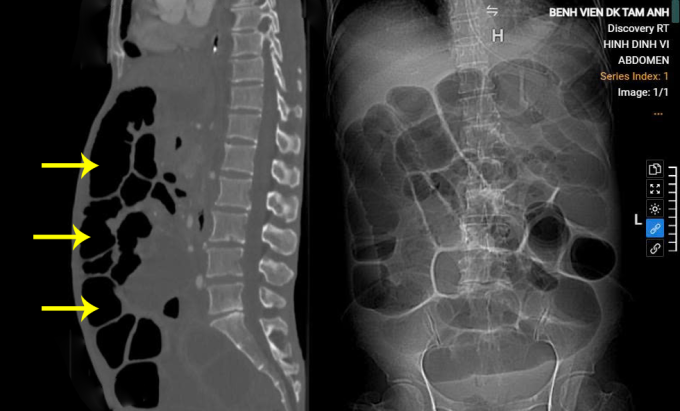

ThS.BS.CKII Lê Văn Lượng, Khoa Ngoại tổng hợp, ghi nhận bụng của bà Hằng chướng căng. Kết quả chụp CT cho thấy ung thư dạ dày đã tiến triển, mức độ di căn xâm lấn toàn bộ đại tràng gây tắc ruột, nguy cơ vỡ ruột gây viêm phúc mạc, nhiễm trùng cao. Song, bác sĩ Lượng đánh giá ruột non chưa bị di căn, có thể phẫu thuật giải quyết tắc ruột, khôi phục nuôi dưỡng qua đường tiêu hóa, nâng cao thể trạng cho người bệnh để tiếp tục điều trị.

Bụng người bệnh chướng khí, ứ đọng dịch tiêu hóa, quai ruột giãn rộng trên ảnh chụp CT. Ảnh: Bệnh viện Đa khoa Tâm Anh